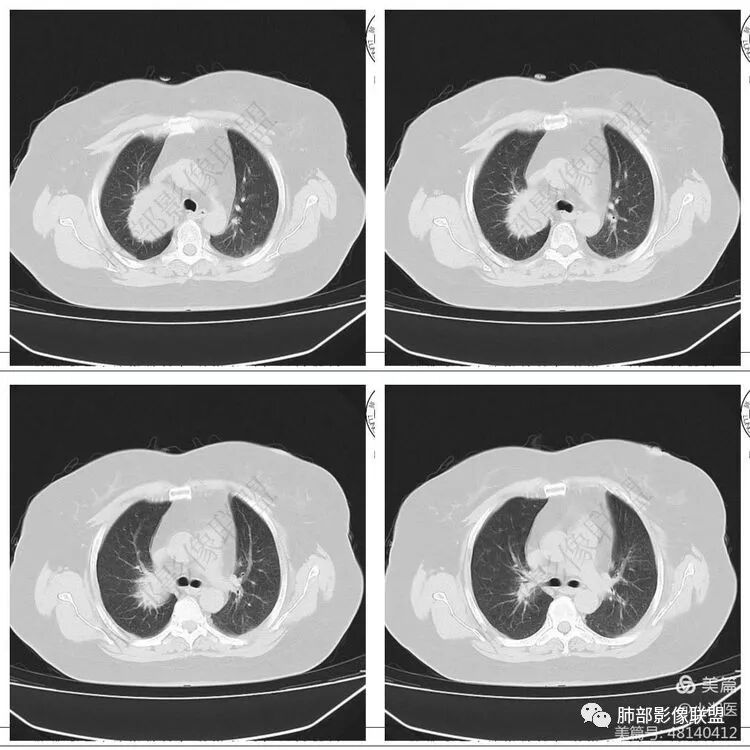

大雄:定位: 纵隔(往左推移气管 往前推移腔静脉 往下推移肺尖胸膜)定性: 良性(边缘光滑,与周围结构境界清晰,无侵袭性生长特点)特征:增强可见AB区(富细胞区与粘液区),延迟强化明显。考虑:神经鞘瘤 ,鉴别:SFTKing:纵隔偏良性肿瘤,与甲状腺无关。首先考虑神经鞘,其他如副节,SFT,巨淋巴待鉴别。飞鹰行动:右侧上胸腔近纵膈类圆形软组织占位,边界清晰光滑,内见囊变,增强渐进性强化,考虑来源纵膈的病变,神经鞘瘤可能,鉴别孤立性纤维瘤。小兜:右上纵隔椭圆形占位,胸膜掀起,肺组织受压,气管受压移位,考虑来源于纵隔,边缘光滑,增强扫描渐进性不均匀强化,内见大片无强化区,考虑为神经鞘瘤可能,鉴别SFT。陈学君:后纵隔占位,多发囊变,渐进強化,考虑鞘瘤,鉴别SFT红星:右上胸廓入口类圆形肿块,肺瘤界面清晰,肺支气管及血管受压,强化不均,片状楔形坏死,考虑来源纵隔占位,神经鞘瘤。鉴别STF、肉瘤?宇宙:右上后纵隔旁椭圆形肿块,边缘光整,向上突入颈根部,肺组织、血管及气管受压移位,密度不均匀,不均匀渐进强化,囊变,考虑神经鞘瘤,鉴别SFT

Kery Wang:

右侧上胸腔近纵膈类圆形软组织占位,边界清晰光滑,考虑来源纵膈的病变,神经源性可能,鉴别孤立性纤维瘤。医然为伱つ:有AB区,首先考虑鞘瘤,鉴别SFT

1. 右上胸廓入口区类椭圆形块影,边界清楚光整,纵向“嵌顿”于颈根部及上纵隔,向上推移右锁骨下动静脉,向外下方推移上肺胸膜及肺组织(肺血管、支气管),向前推移上腔静脉,界限清楚。

2. 块影不均匀轻度强化,可见较均匀实性区及液性密度区,未见积气、囊壁样结构、钙化或脂肪密度。可疑部分肋间动脉分支进入。

3.块影相邻椎骨及肋骨明确推压或骨质吸收破坏,未见椎管内结节或椎间孔扩大。

4.双肺门及纵隔未见肿大淋巴结。